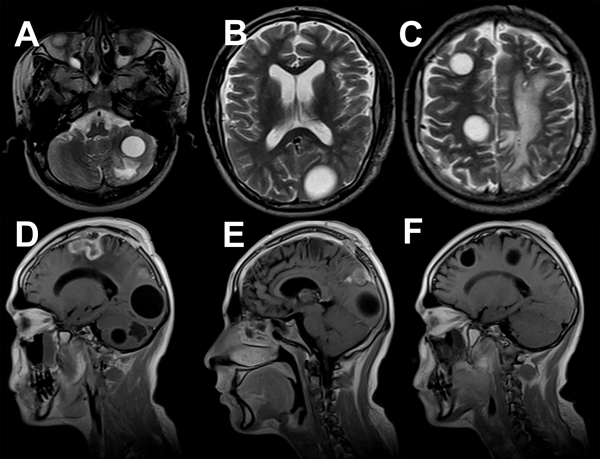

En el control postoperatorio a los 6 meses, todavía en tratamiento antiparasitario, el paciente no presentó deterioro clínico y la resonancia magnética de control mostró la disminución del tamaño de una de las lesiones preexistentes en fosa posterior sin modificaciones en las restantes (Figura 5). Ante estos hallazgos, se propuso la reintervención de las lesiones remanentes, pero el paciente rechazó el procedimiento.

Figura 5. A) RM T2 axial postoperatoria (6 meses). Se evidencia disminución del tamaño quístico en hemisferio cerebeloso. B-C) RM T2 axial. Se muestran cambios postoperatorios y quistes remanentes de igual tamaño. D-F) RM T1 con contraste sagital postoperatorias (6 meses). Se visualiza realce con contraste en lodge quirúrgica y remanentes quísticos de similares características.